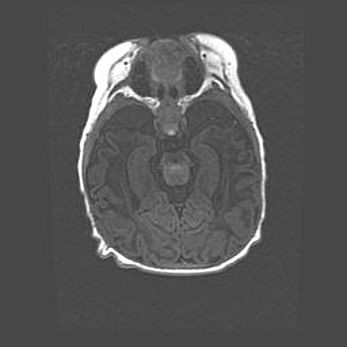

Мальформация Денди-Уокера. Киста задней черепной ямки.

Агенезия мозолистого тела.

Возраст: 2,5 месяца

Вес: 2420 г

Пол: женский

Окружность головы: 37 см

Срок гестации: 32 недели

Мальформация Денди—Уокера — редкий вид патологии ЦНС, представляющий собой врожденный порок развития каудального отдела ствола и червя мозжечка, ведущий к неполному раскрытию срединной (Мажанди) и латеральных (Лушка) апертур IV желудочка мозга. Для этогно синдрома характерна триада симптомов: гипотрофия червя мозжечка и/или полушарий мозжечка, кисты задней черепной ямки, гидроцефалия различной степени. В 70% случаев порок сочетается и с другими аномалиями головного мозга, в частности с агенезией мозолистого тела.